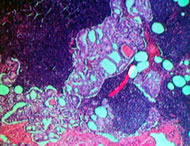

Лекция: "Прогностические факторы при раке предстательной железы".

система стадирования (TNM)